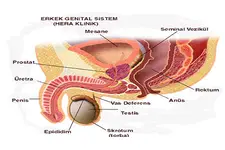

Genital tüberkül, tüberküloz hastalığına neden olan Mycobacterium tuberculosis bakterisinin yol açtığı genital sistemdeki enfeksiyonları ifade eder. Genital tüberküloz, genellikle akciğer tüberkülozunun bir komplikasyonu olarak ortaya çıkar; ancak, primer genital enfeksiyonlar da mümkündür. Bu makalede, genital tüberkül türleri ve özellikleri detaylı bir şekilde ele alınacaktır. Genital Tüberkül Türleri Genital tüberkül, çeşitli alt türlere ayrılabilir. Bu türler, enfeksiyonun yerleşim yeri ve hastalığın seyrine göre değişiklik göstermektedir. Aşağıda, genital tüberkül çeşitleri ve özellikleri sunulmuştur: